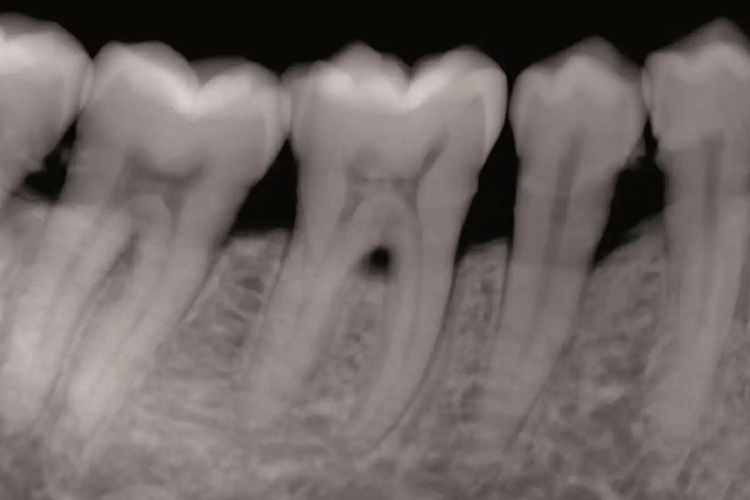

上颌前磨牙根尖片为临床最常用的牙影像检查方法,主要显示牙体、牙髓腔、根管及根尖周组织等。牙片大小为3cm×4cm,一张牙片可了解上颌前磨牙的根周、根管及牙冠等情况。正常上颌前磨牙的轮廓线清晰、完整且连续,其中牙釉质密度最高,牙髓腔密度最低,牙本质居中。牙槽骨内显示出网状骨纹理,牙周膜显示为牙根周围的低密度线影,正常牙龈一般不显影。

在临床上通过上颌前磨牙根尖片可了解牙体、牙周、牙髓组织及根尖周组织的病变情况,具有放射剂量小、空间分辨率高、操作简便等优点,是龋病治疗和根管治疗中最常用到的X线检查。